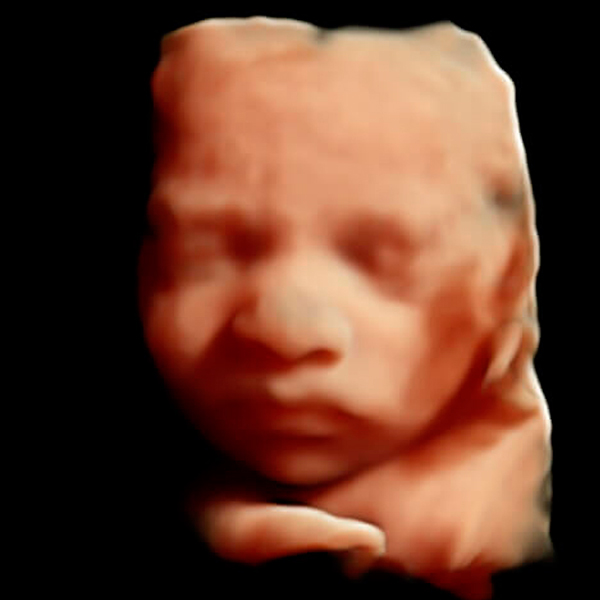

Actualmente realiza un Doctorado Internacional en Medicina Fetal avalado por las universidades de KU Leuven (Bélgica), Universidad de Barcelona (España) y la Universidad de Lund en Suecia, tres instituciones líder en el segmento de la medicina fetal a nivel mundial.